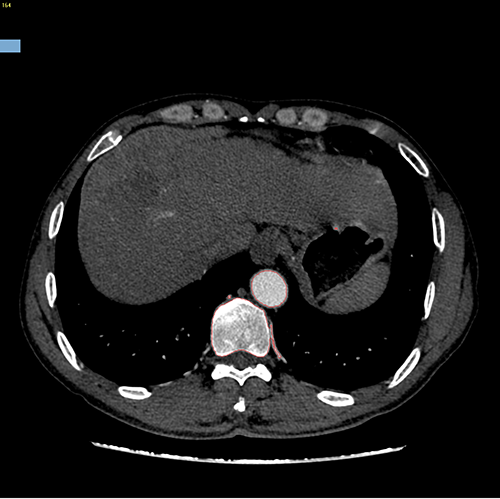

右肝癌---右三肝切除

介入后2周